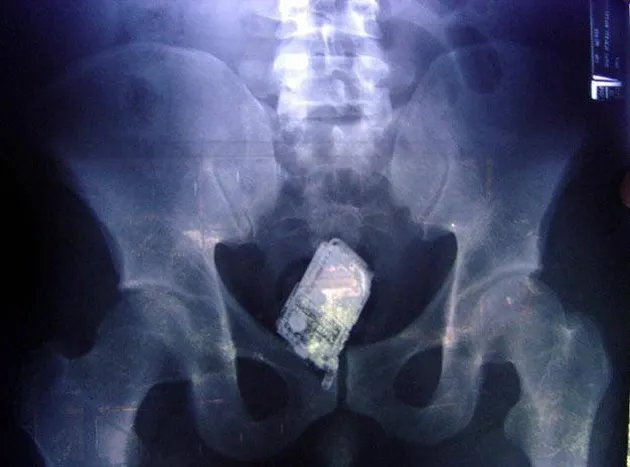

Entah bagaimana awalnya, seorang pengacara dari Georgia harus menerima kenyataan jika ada handphone di dalam tubuhnya. Lucunya, handphone tersebut sempat berdering beberapa saat sebelum dikeluarkan melalui operasi. Well, sepertinya handphonenya tahan air...